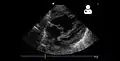

Echocardiography

If pulmonary hypertension is suspected based on the above assessments, echocardiography is performed as the next step.[11][12][54] A meta-analysis of Doppler echocardiography for predicting the results of right heart catheterization reported a sensitivity and specificity of 88% and 56%, respectively.[56] Thus, Doppler echocardiography can suggest the presence of pulmonary hypertension, but right heart catherization (described below) remains the gold standard for diagnosis of PAH.[11][12] Echocardiography can also help to detect congenital heart disease as a cause of pulmonary hypertension.[11]

4 month old with pulmonary hypertension as seen on ultrasound[57]